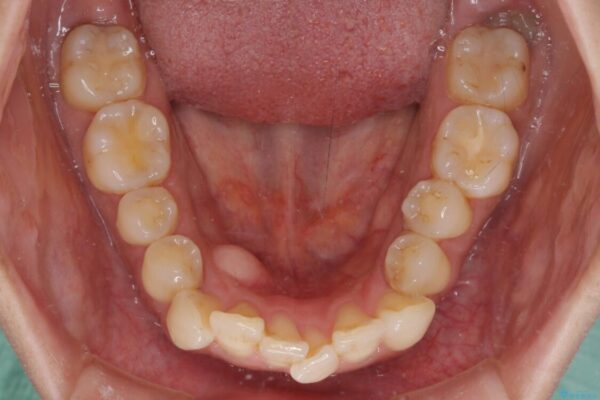

治療前

• インビザラインによる矯正治療と奥歯のインプラント治療 治療前画像